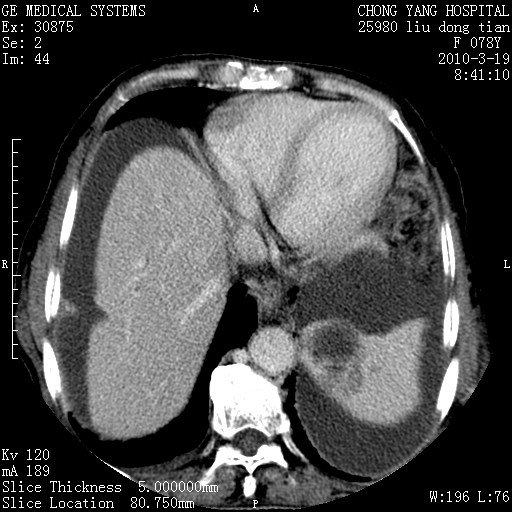

标题: CT25199:F 78Y 腹胀半年 消瘦乏力 [打印本页]

胆囊壁增厚并明显强化,胆囊癌伴多发转移瘤可能性大,淋巴瘤不除外,右肾囊肿,胸腹水.

考虑nhl,肝、脾、腹膜腔及腹膜后多发淋巴结受侵,腹水,右肾囊肿,慢性胆囊炎,右侧少量胸腔积液。

胆囊有软组织影有强化,支持胆囊癌,肝脾、腹膜后淋巴结转移。

分开来讲:肝左叶、尾叶病灶有不均强化像肝癌;

脾脏病灶无强化,像多发囊肿或淋巴管瘤,不除外淋巴瘤(低强化);

肝门、胰腺头、腹膜后多个团块: 淋巴瘤,转移;

一元论最好了 淋巴瘤所致改变; 胆囊癌转移不像,胆囊周围肝组织清晰,肝癌淋巴结转移?三元论都不止。

最后报的胰头癌多发转移,脾脏单独考虑囊肿或淋巴管瘤。